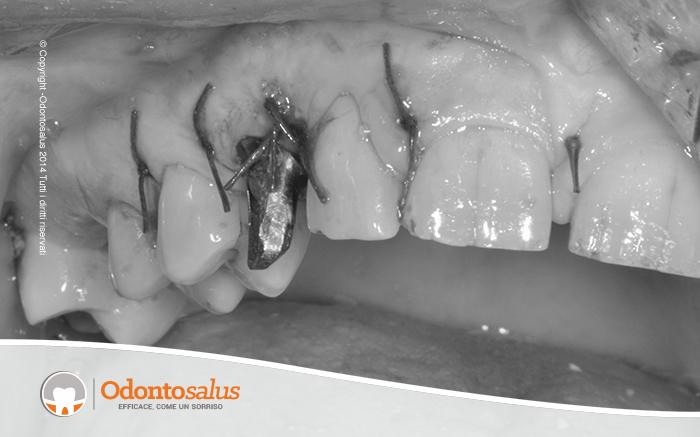

Inizialmente è stato effettutao un trattamento ortodontico per riportare l’elemento incluso in arcata. Tuttavia, come a volte accade in relazione all’età del paziente, alla densità ossea o alla posizione del dente incluso, ortodonticamente non è stato possibile riallineare il canino con gli altri denti. Si è proceduto, pertanto, con l’incisione del lembo, la scopertura e l’estrazione del canino, il riempimento del deficit osseo creato, l’applicazione dell’impianto e, data la sua stabilità, l’inserimento del provvisorio nella stessa seduta.